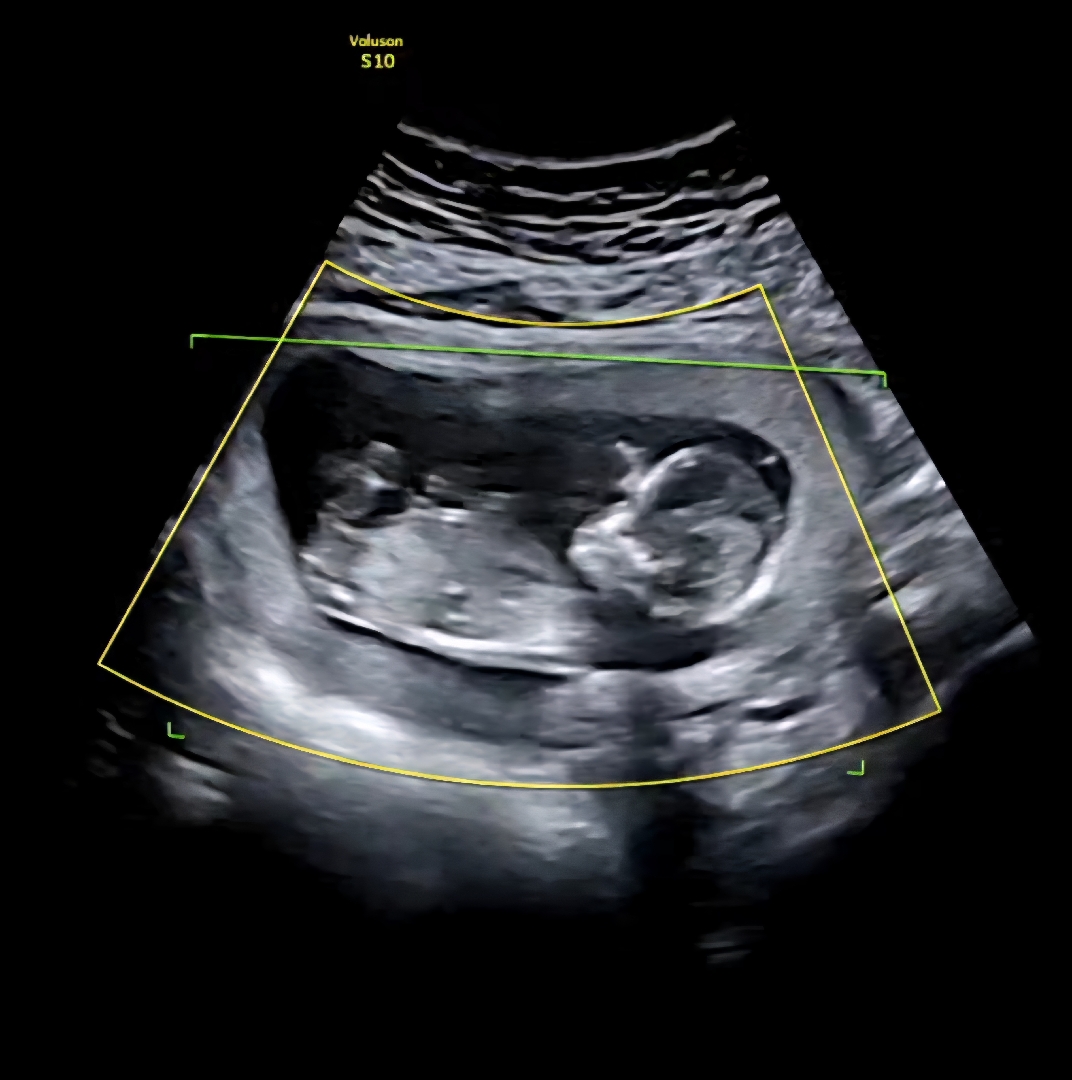

13주 1일 각도법 봐주세요!

저는 봐도 잘 모르겠어서요 잘 보시는 분 각도법 부탁드려요~!